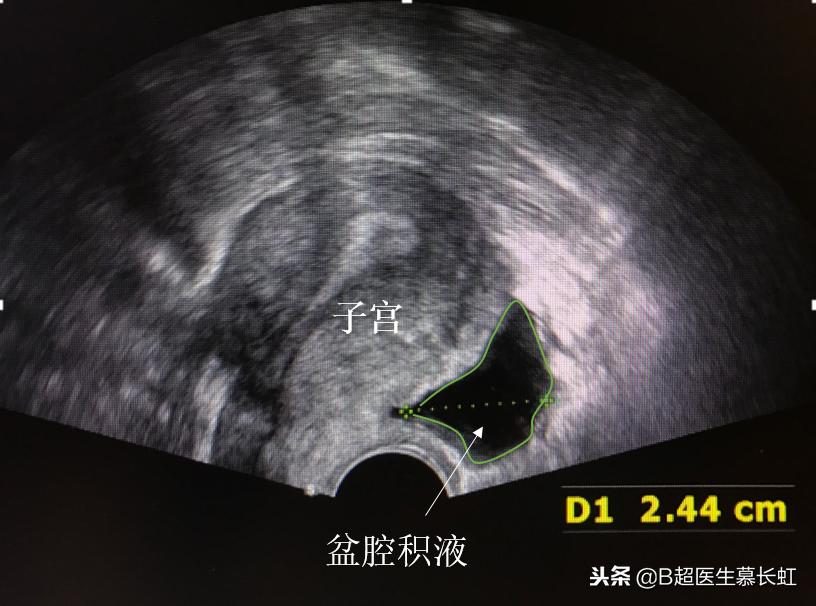

是测量子宫后方直肠子宫陷凹那个位置的液体的深度。由于子宫后方的直肠子宫陷凹是盆腹腔最低的位置,所以盆腹腔的液体最容易积聚在子宫后方。

而女性在月经期或者排卵期的时候,子宫后方也会有积液,月经期是由于盆腔充血渗出一点点液体。排卵期是因为排卵时卵泡破裂,里面的卵泡液流出积在子宫后方。这种生理性盆腔积液一般深度也就1-3cm。

盆腔积液